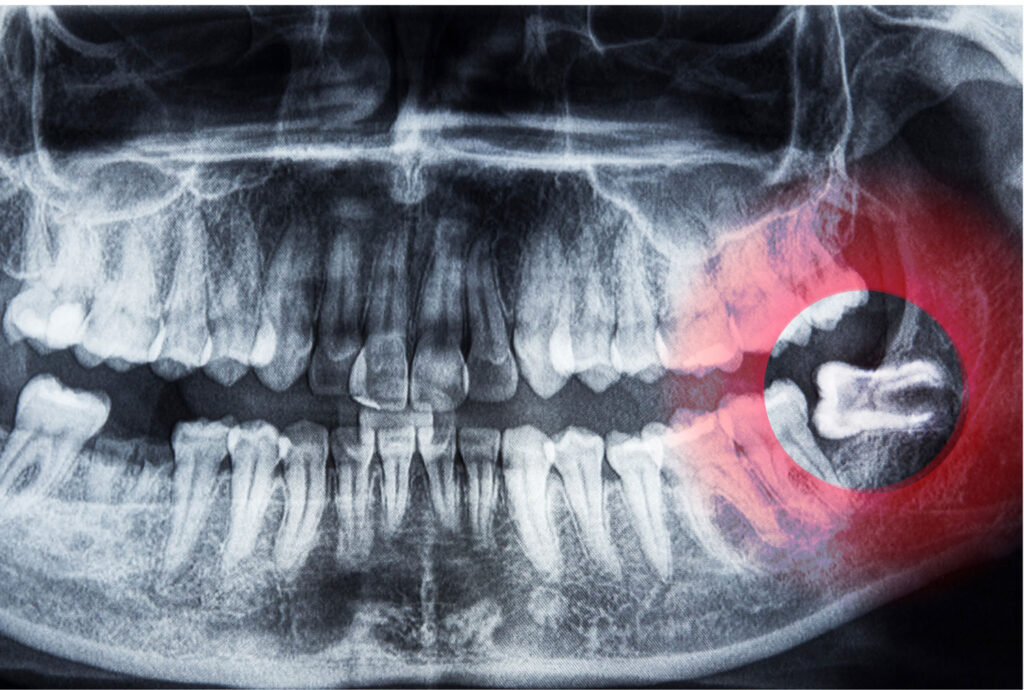

Impaction

Tooth impaction occurs when the growth of one tooth pushes directly against another. The tooth is susceptible to infection, causing red, swollen, tender, or bleeding gums. People who experience this condition often report pain and swelling around the jaw and difficulty opening their mouths.

Typically, the culprit for this condition is the wisdom teeth, the third set of molars that don’t have enough room in the mouth to grow upright, so they instead grow inward toward the rest of the teeth. In these cases, it is best to have the wisdom teeth removed as soon as possible to prevent further damage to the other teeth.